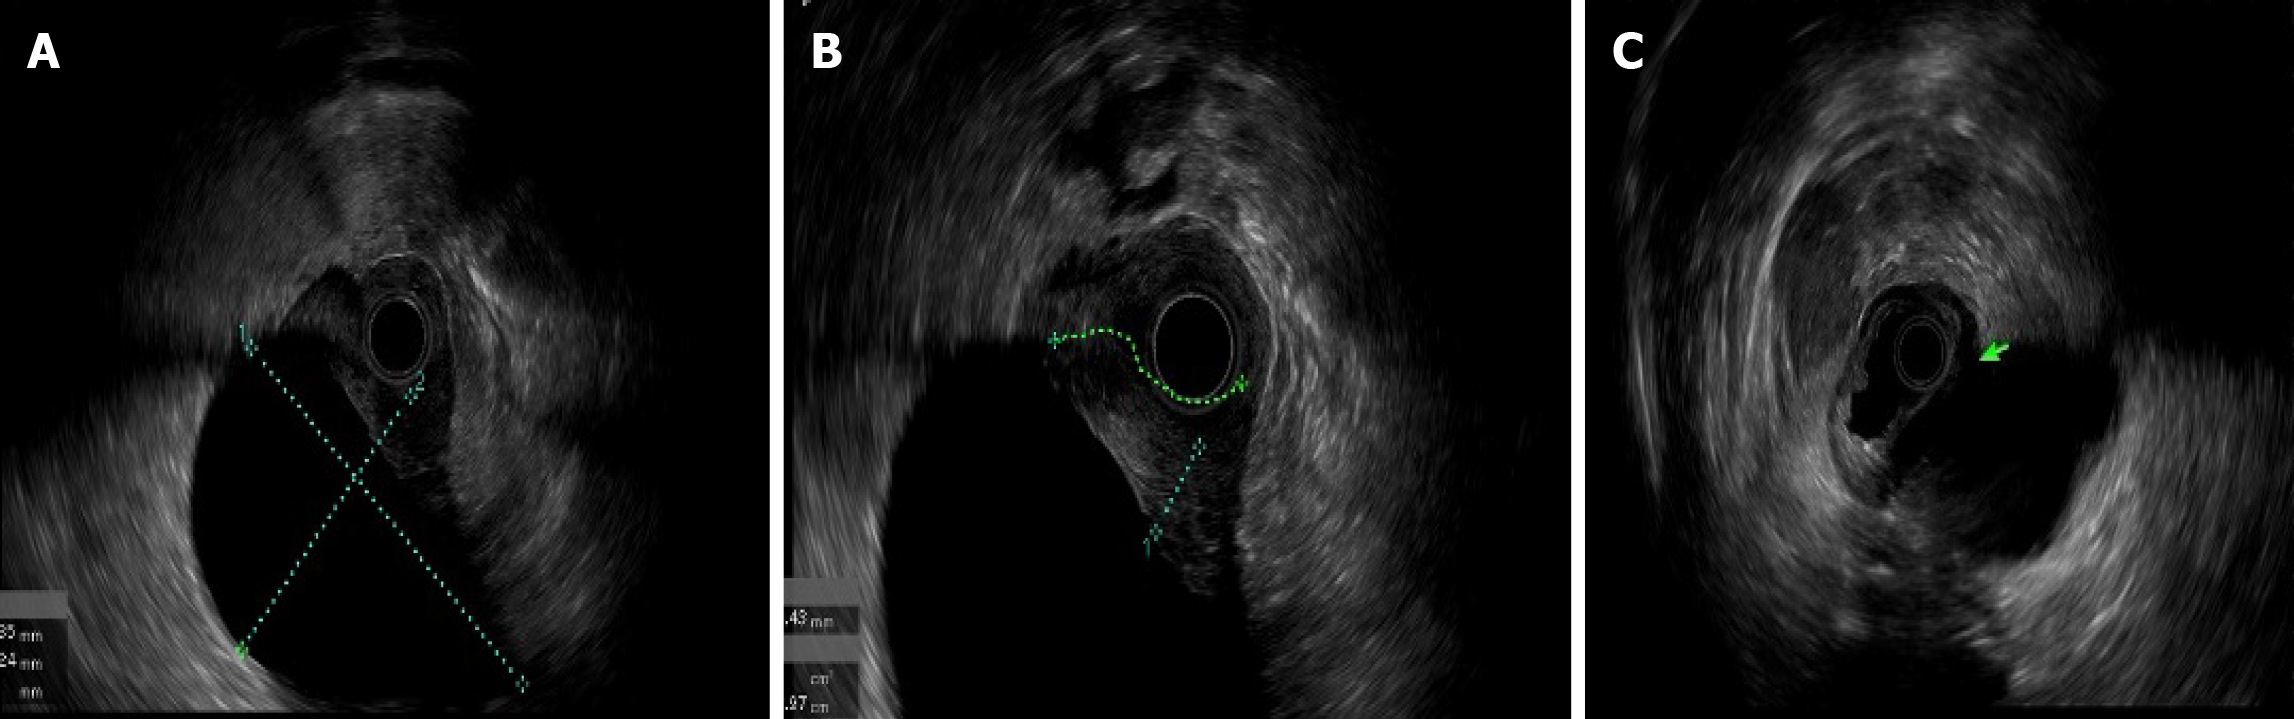

An upper endoscopy revealed the following: (1) A large, soft submucosal lesion involving the pylorus and greater curvature of the gastric antrum, with preserved luminal patency; (2) An ulcerated lesion at the duodenal bulb-descending junction, with luminal narrowing and raised margins (Figure 3); and (3) Endoscopic ultrasonography (EUS) identified a 7 cm × 4.8 cm mixed cystic-solid mass with clear demarcation from the adjacent organs but a loss of interface with the fourth layer of the gastric wall (Figure 4).

Among the reviewed cases, we found that the morphology of adenocarcinomas arising from HP varies considerably. Preoperative diagnosis of a malignant ectopic pancreas with stenotic or submucosal tumor (SMT) morphology and no ulceration can be difficult using imaging studies such as CT and radiography. This is because imaging can only indicate the presence of a mass; it cannot determine its nature. For this reason, most of the reviewed cases of adenocarcinomas arising from an ectopic pancreas were resected as SMTs with tentative diagnoses of gastrointestinal stromal tumor, lymphoma, or other[4]. The mass in our patient had a predominantly SMT-like appearance, with focal ulceration in the duodenum. Malignant transformation of an HP usually occurs intramurally, and involvement of the overlying mucosa occurs late in the course of the disease. While upper endoscopy with conventional biopsy at the location of the tumor rupture can obtain pathological findings, it often fails in SMT-like lesions. The utility of EUS-FNA and endoscopic mucosal resection with cap for histological diagnosis has been demonstrated for many gastrointestinal and pancreatic malignancies. EUS is especially helpful in the diagnosis of SMTs. EUS-FNA combined with immunohistochemistry can achieve a higher histological diagnostic rate. An endoscopic mucosal resection with cap is an endoscopic mucosal resection performed using a panendoscope with a fitted transparent plastic cap. This, followed by a biopsy[4], should be considered before selecting a treatment approach. Matsuki et al[5] have reported a case with no distinct cystic lesion on EUS due to its obscuration by severe stenosis. Therefore, although EUS is generally helpful for the diagnosis of SMTs, the location of the tumor may determine the clarity of the scan. The detection of cystic components inside the tumor is helpful for the diagnosis of HP[5].